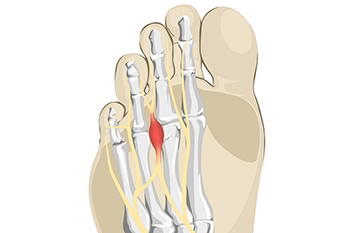

What Causes Morton’s Neuroma?

The foot condition that is known as Morton’s neuroma is painful. It is caused by wearing shoes that do not have enough room in the toe area and it affects the nerve between the third and fourth toes. High heels can fall into this category, and women can develop this condition if high heels are worn often and for long periods of time. Patients may feel this affected nerve can be malignant, however, it is considered to be a benign growth. The pain is often felt in the ball of the foot, and it may be difficult to walk. Temporary relief may be found when wider shoes with lower heels are worn. There may be swelling that accompanies this ailment, and it can be helpful to elevate the feet. In severe cases, some patients may choose surgery that can remove the nerve, and normal activities may be resumed. If you have foot pain from for Morton’s neuroma, it is strongly suggested that you contact a podiatrist who can effectively diagnose and offer the correct treatment methods.

Morton's neuroma is a painful foot condition that commonly affects the areas between the second and third or third and fourth toe, although other areas of the foot are also susceptible. Morton’s neuroma is caused by an inflamed nerve in the foot that is being squeezed and aggravated by surrounding bones.